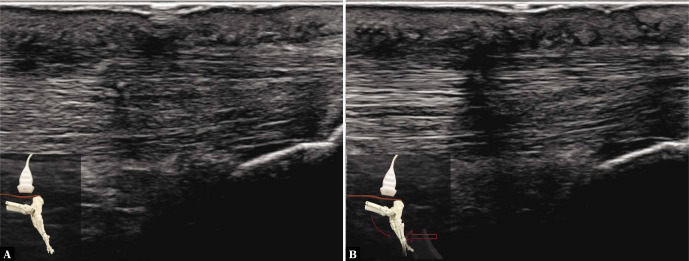

A continuación, puedes observar una imagen ecográfica de un paciente operado hace 3 meses por una ruptura del tendón de Aquiles. En la izquierda el tendón estaría en reposo y en la derecha estaría haciendo una flexión plantar contraresistencia.

Como se observa, las fibras del tendón son lineales al aplicar resistencia, sin ondulación alguna, lo que indica una buena función del tendón.